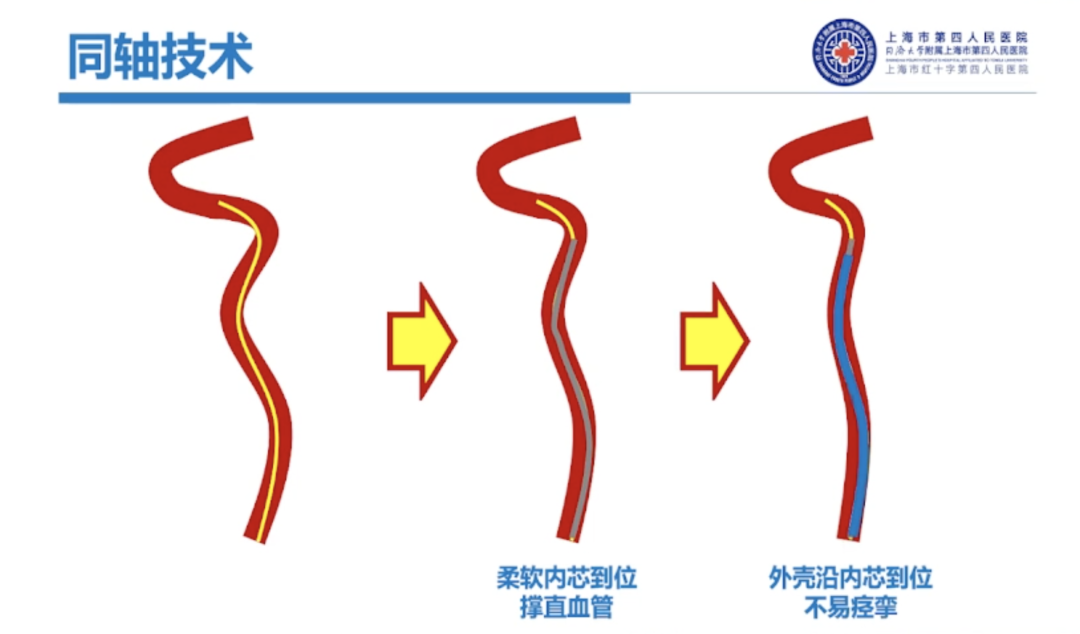

早期同轴技术的应用:在使用粗导管过弓时使用同轴技术来克服窗台效应,减少局部块脱落,增加导管通过的成功率。

过往的同轴技术是柔软内芯+相对支撑良好的外管,而R-DAS技术恰恰相反,是硬内芯(支撑)+软外管(建立通路)的组合。